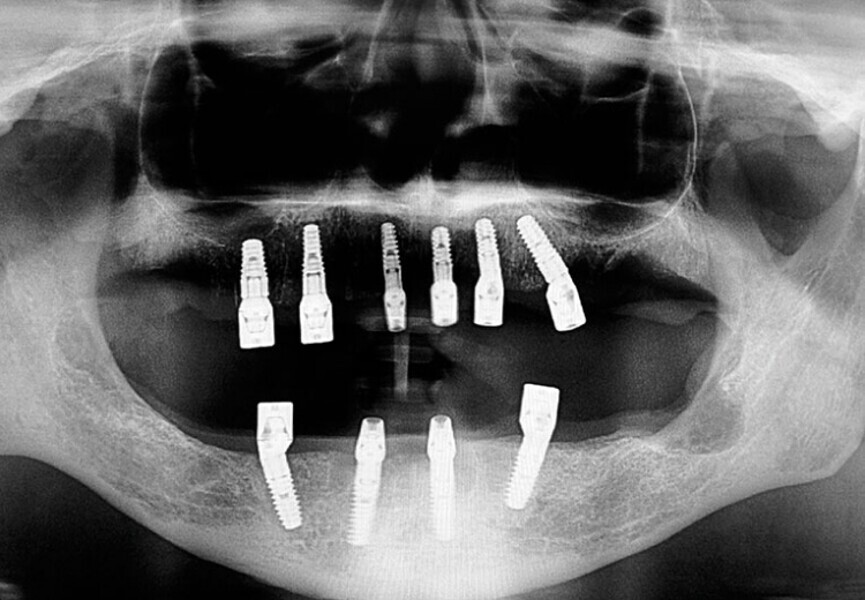

Protocollo SKY fast & fixed